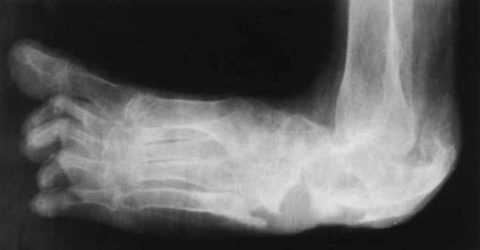

| Признаки диабетической стопы проявляются при снижении чувствительности стопы, повышении болевого порога, изменении формы, деформации, утолщении кожи и появлении мозолей (чаще на головках II-III метатарзальных костей) и сопровождаются гиперкератозом и сухостью кожи, незначительными болями или без них. Стопа Шарко или периферическая нейропатия провоцирует развитие остеоартропатии – синдромокомплекса с асептической костной деструкцией суставов и костей, что можно увидеть на рентгенограмме. При этом страдают голеностоп, плюсна и предплюсна:

Длительный деструктивный остеопороз, остеолиз, гиперостоз приводит к синдрому диабетической стопы: деформации костей, суставу Шарко. Тогда стопа будет напоминать мешок с косточками. Понадобятся срочное лечение и ортопедическая обувь.

- рентгенографии,